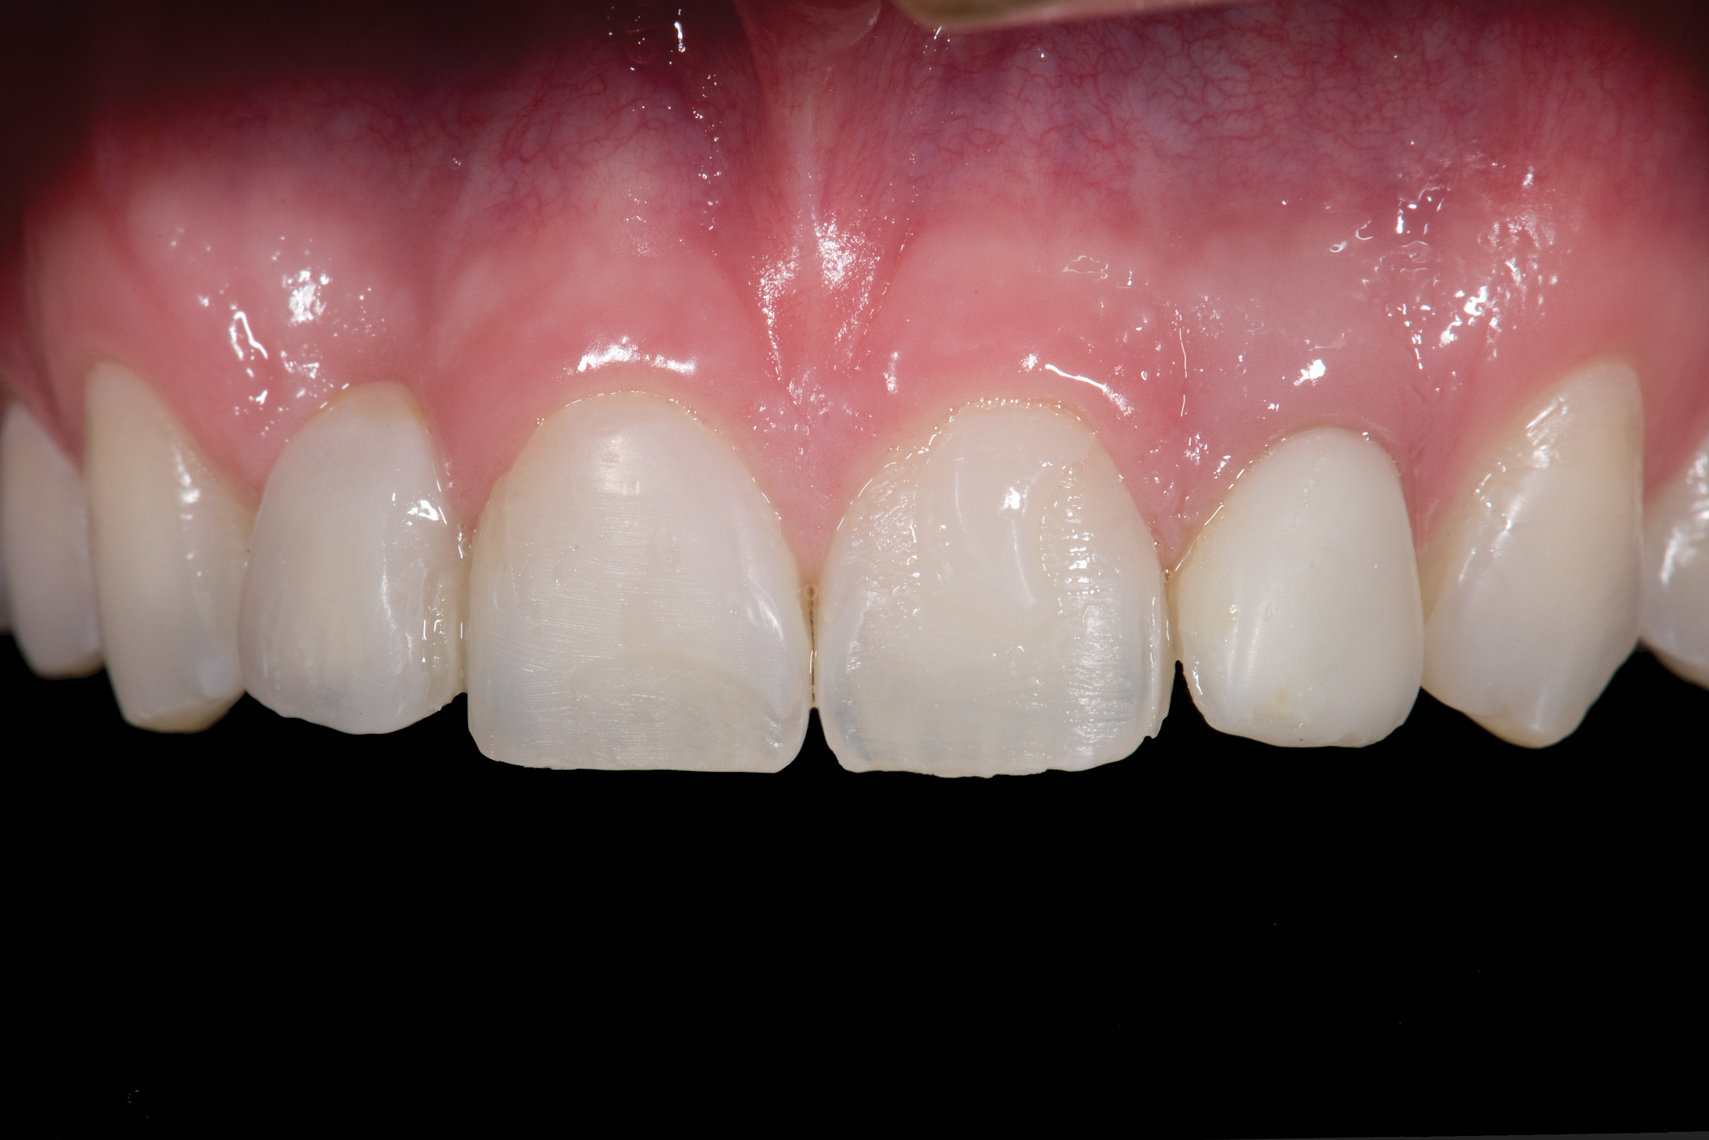

Fig 20. Facial view of final single-wing, modified zirconia resin-bonded bridges.

Figure 20

Fig 21. Smile view.

Figure 21

When the patient returned, the fit was evaluated in the mouth. Once verified, the internal surface of the framework was etched with a 9.5% hydrofluoric acid for 90 seconds and then salinized. After etching the enamel surface with phosphoric acid for 30 seconds and applying the primer (Single Bond Plus, 3M ESPE) to both the internal surface of the framework and the enamel, the zirconia bridge was bonded with a dual-cure resin cement (RelyX ARC, 3M ESPE). After the procedure, the patient ended up with a long-term, high-strength esthetic restoration advantaged by the bonding potential of feldspathic ceramic (Figure 20 through Figure 24). Six years after placement, the prosthesis had remained in place with no complications.